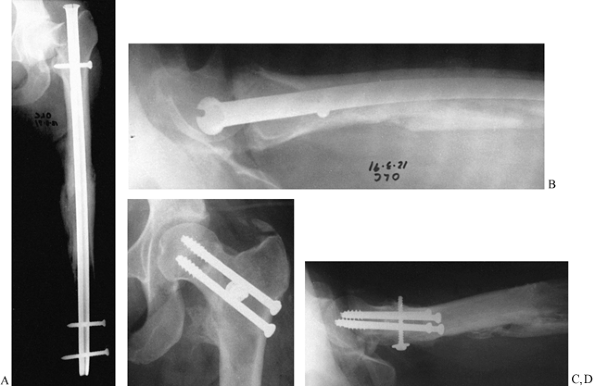

Figure 29.9. A:

AP radiograph of the femur of a 50-year-old man who was treated for a chondrosarcoma of the femur 9 months earlier. The tumor in the mid shaft was resected; the shaft was autoclaved and reconstructed. There is a nonunion at the subtrochanteric junction, with subsidence into varus. B: The postoperative radiograph shows reconstruction by replacement of the dead diaphysis with an allograft and fixation with an Alta rod connector using a dome in the hip. The graft junction sites were grafted with autologous bone. |